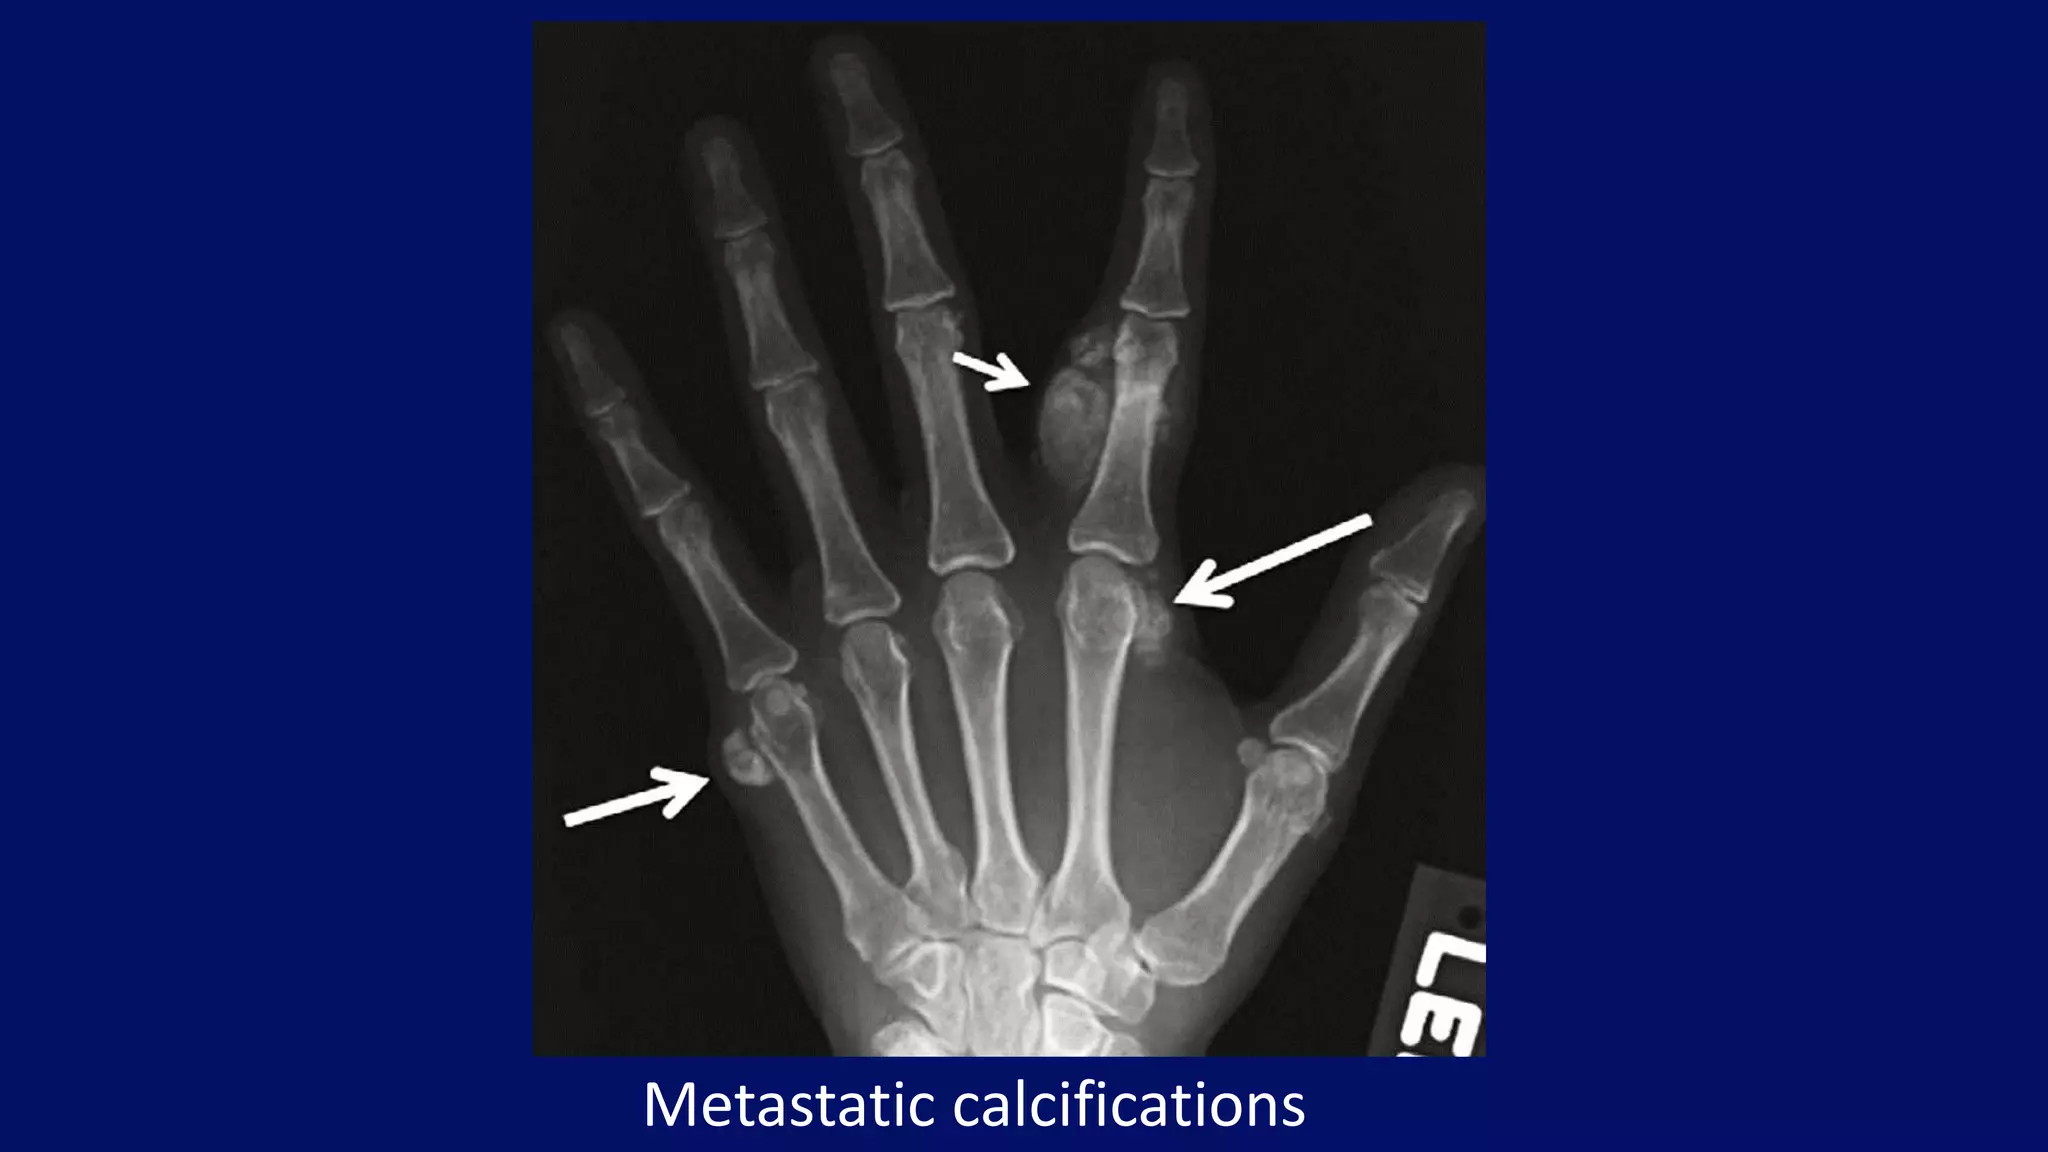

Metastatic calcifications

• #106 Phosphate retention leads to increase in the phosphate × calcium product and precipitation of amorphous calcium phosphate in the arteries and soft tissues. AP radiograph of the left hand shows metastatic calcificationsaround the second and fifth metacarpophalangeal joints (large arrows) and along the second proximal phalanx (small arrow). More typically these calcifications are seen around the large joints.